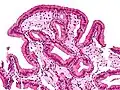

Micrografia da colesterolose da vesícula biliar. Mancha de H&E.

Na patologia cirúrgica, vesícula biliar de morango, mais formalmente colesterolose da vesícula biliar e colesterolose de vesícula biliar, é uma alteração na parede da vesícula biliar devido ao excesso de colesterol.[1]

O nome vesícula biliar de morango vem da aparência tipicamente pontilhada da superfície da mucosa, em um exame grosseiro, que se assemelha à aparência de um morango.